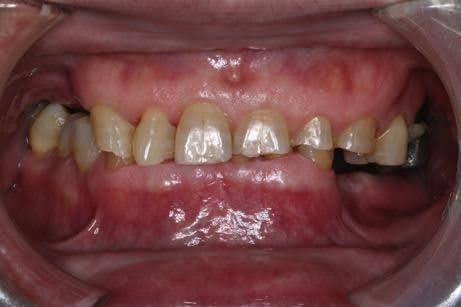

症例